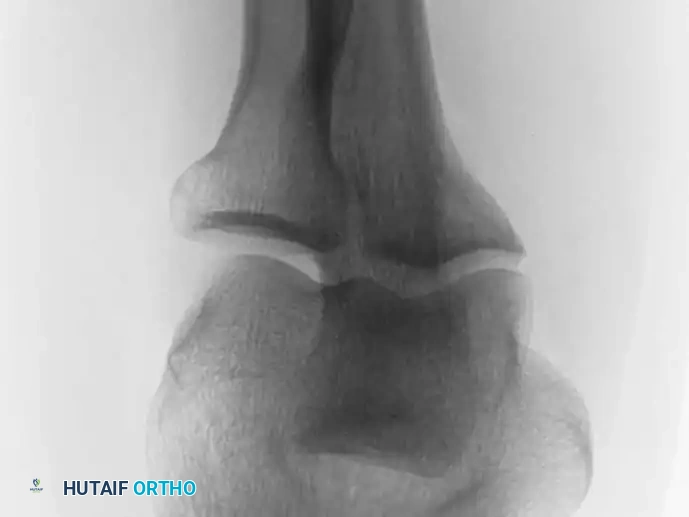

Intraoperative Imaging and Margin Assessment

Continuous intraoperative assessment using fluoroscopy and frozen section pathology is mandatory. The following images demonstrate various stages of complex upper extremity resections, allograft preparations, and prosthetic implantations across the humerus and elbow joint.

Distal Humerus and Elbow Reconstruction

When tumors involve the distal humerus, resection often requires sacrifice of the collateral ligaments and the articular surface of the elbow. Reconstruction is typically achieved using a linked, semi-constrained total elbow arthroplasty designed for oncologic defects.